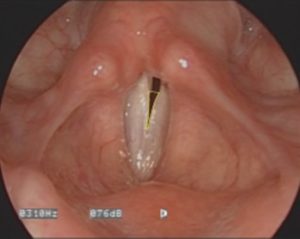

後方ギャップのある声門閉鎖

研究では、若年女性の約85%以上において、知覚上「息っぽさ」がないにも関わらず、ストロボスコピーで後方にわずかな開き(後方ギャップ)が確認されています。つまり、女性の後方ギャップは生理的に自然な現象であり、必ずしも音質や健康に悪影響を与えるものではありません。

プロフェッショナル歌手が意図的に「息っぽさ」を演出する場合、典型的な後方ギャップではなく声帯の長さに沿った帯状のギャップを形成する傾向が確認されています。

この違いは、「閉じていない=悪い」ではなく、どの位置にどのようなギャップがあるかが歌声に決定的な影響を与えることを示しています。

後方ギャップを使わない「息っぽい歌声」の声門閉鎖